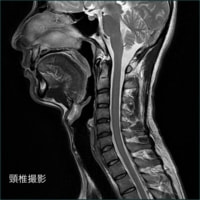

<放射線部の特徴と検査内容>

平成25年より新しく稼働したCT、MRIを始め、マンモグラフィー、骨密度測定、レントゲン画像装置などにより病気の早期発見、早期診断を目指しています。

軟部組織のコントラストに優れ、様々なコントラストパラメーターを有するMRIは、頭頚部、体幹部、脊椎・脊髄、整形領域、心臓領域とほぼ全身に渡る断層画像をあらゆる角度で撮像できます。

MRIの画像